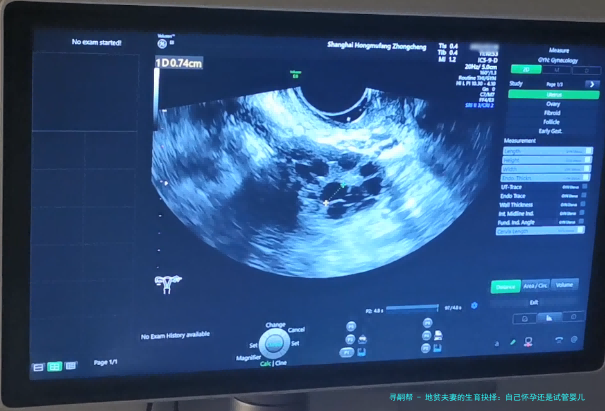

接下来,咱们聊聊试管婴儿技术。试管婴儿,学名叫体外受精-胚胎移植,特别是其中的PGD(植入前遗传学诊断)技术,简直就是地贫夫妻的救星。简单来说,医生可以在实验室里对胚胎进行基因筛查,只选择没有地贫基因的健康胚胎移植到子宫里。这样,就能大大降低孩子患病的风险。在我看来,这就像是为生育之路装上了“导航系统”,让你避开那些遗传陷阱。举个例子,前面提到的小张和小李后来选择了试管婴儿,通过PGD筛查,他们成功生下了健康的宝宝,现在家庭生活美满。不过,试管婴儿也有它的缺点,比如费用较高,过程可能比较繁琐,而且成功率不是100%。但总的来说,对于高风险的地贫夫妻,它提供了一个更安全的选项。